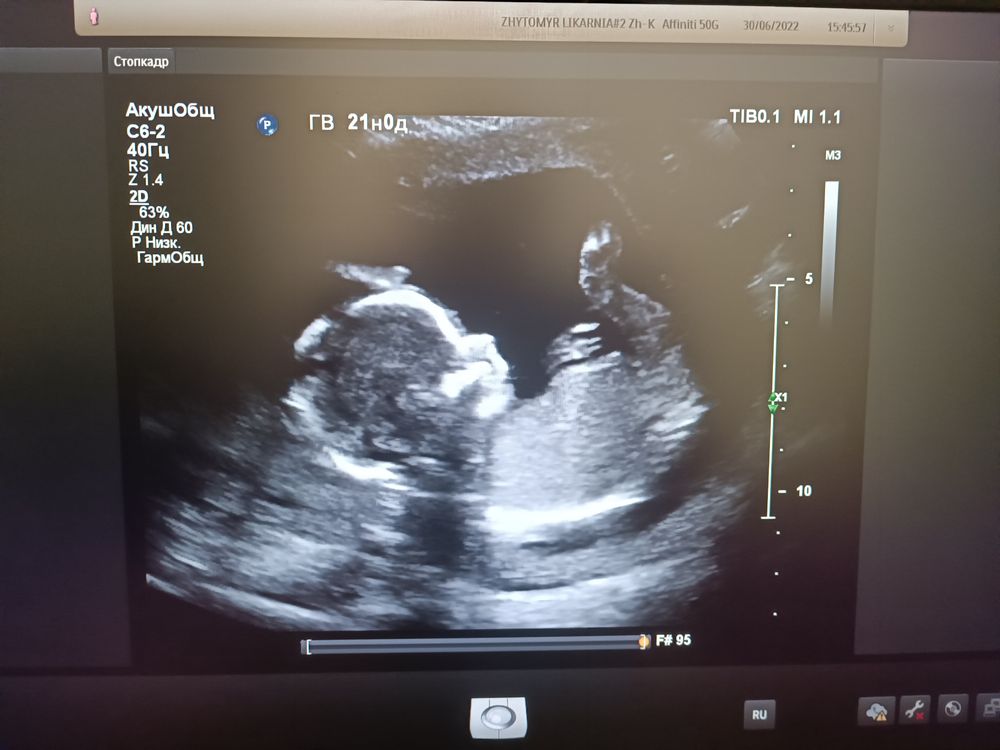

Девочки,мы сегодня сходили всё-таки на дополнительное УЗИ для определения пола, узист отнеслась с пониманием,высмотрела все ,написала на листике,конверт отдала,мы уже отнесли его девочке-продавцу ,где приготовят наш шарик с заветным цветом) Папа старался не смотреть на экран,но одно фото сделали и небольшое видео,но вроде бы как ничего на нем не видно (специально,чтобы раньше времени не испортили себе сюрприз)))) Фото с УЗИ прикрепляю. Нам сегодня 16 недель и 3 дня (хоть там написано больше, почему-то). Все равно,конечно, интересно. Жду ваших предложений 🙂

30.06.2022